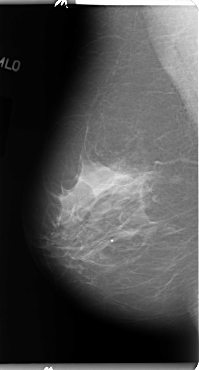

B_3114_1.RIGHT_MLO

ics_version 1.0

filename B-3114-1

DATE_OF_STUDY 12 7 1996

PATIENT_AGE 57

FILM_TYPE REGULAR

DENSITY 2

DATE_DIGITIZED 22 1 1998

DIGITIZER LUMISYS LASER

RIGHT_MLO LINES 4808 PIXELS_PER_LINE 2584 BITS_PER_PIXEL 12 RESOLUTION 50 NON_OVERLAY